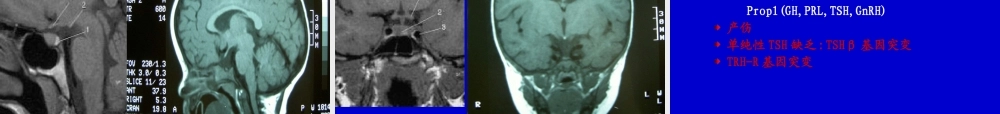

小儿甲状腺疾病重庆医科大学儿童医院内分泌科朱岷甲状腺功能低下症甲状腺功能亢进症甲状腺炎小儿甲状腺功能低下症小儿甲低分类先天性获得性散发性地区性暂时性永久性原发性→甲状腺继发性→垂体→下丘脑周围性→甲状腺素抵抗先天性甲状腺功能低下症(CH)最常见的小儿内分泌疾病之一:1/3500-4000最严重的后果→终生不可逆智力低下可预防性智力低下的最常见原因早期治疗可避免智力低下新生儿筛查使早期诊断治疗成为可能大多数为散发性,少数为家族遗传性,可为地方性(缺碘)最常见病因是甲状腺发育不良胎儿的甲状腺素分泌与生后变化甲状腺胚胎发育舌下的中央原基+两侧的第4咽囊移行致颈前(5-7周)甲状腺形成于12周,并开始摄碘甲状腺18-20周产生甲状腺素下丘脑-垂体-甲状腺轴建立并分泌TSH于18周胎儿的甲状腺素分泌与生后变化甲状腺激素与中枢神经系统发育胚胎早期致生后3-4岁是中枢神经系统发育关键期,甲状腺素作用相关基因起重要作用两个关键期孕后3月早期新生儿早期甲状腺激素与中枢神经系统发育胎儿期CNS发育相对独立于胎儿甲状腺,而与母体甲状腺功能密切相关无甲状腺胎儿出生时基本正常孕母甲低(严重缺碘,甲炎),胎儿CNS受损严重胎儿期CNS发育的保护机制母源性T4可通过胎盘胎脑富含二型脱碘酶,甲低时活性上调使T4→T3甲状腺激素与中枢神经系统发育生后及时替代治疗,可避免患儿的智力低下早期诊断治疗的重要性孕母甲状腺功能对胎儿脑发育的重要性对患甲状腺疾病孕母的甲状腺功能检查的重要性CH的病因甲状腺发育不全(原发性甲低)80%甲状腺素合成缺陷(原发性甲低)10%下丘脑-垂体性甲低(中枢性甲低)少见甲状腺素抵抗(周围性甲低),罕见暂时性甲低碘缺乏(地方性甲低)CH的病因甲状腺发育不全(80%)T3↓T4↓TSH↑多为散发,其机制不明少为家族遗传:TTF1、TTF2、PAX8其中异位甲状腺60%(多为舌下),无甲状腺30-35%,正常位置发育不良甲状腺5-10%注意甲状舌骨囊肿中可有异位甲状腺CH的病因甲状腺发育不全(原发性甲低)80%甲状腺素合成缺陷(原发性甲低)10%下丘脑-垂体性甲低(中枢性甲低)少见甲状腺素抵抗(周围性甲低),罕见暂时性甲低碘缺乏(地方性甲低)甲状腺激素合成过程CH的病因甲状腺素合成缺陷(10%)多伴甲状腺肿大可有家族史,T3↓T4↓TSH↑TSH抵抗:TSH受体基因突变G蛋白失活性突变→假性甲旁减,Albright骨病碘摄取缺陷:NIS基因突变过氧化酶系统缺陷(有机化缺陷):TPO多见Pendred综合征:氯-碘转运蛋白基因突变伴耳聋甲状腺球蛋白合成缺陷脱碘酶缺陷CH的病因甲状腺发育...